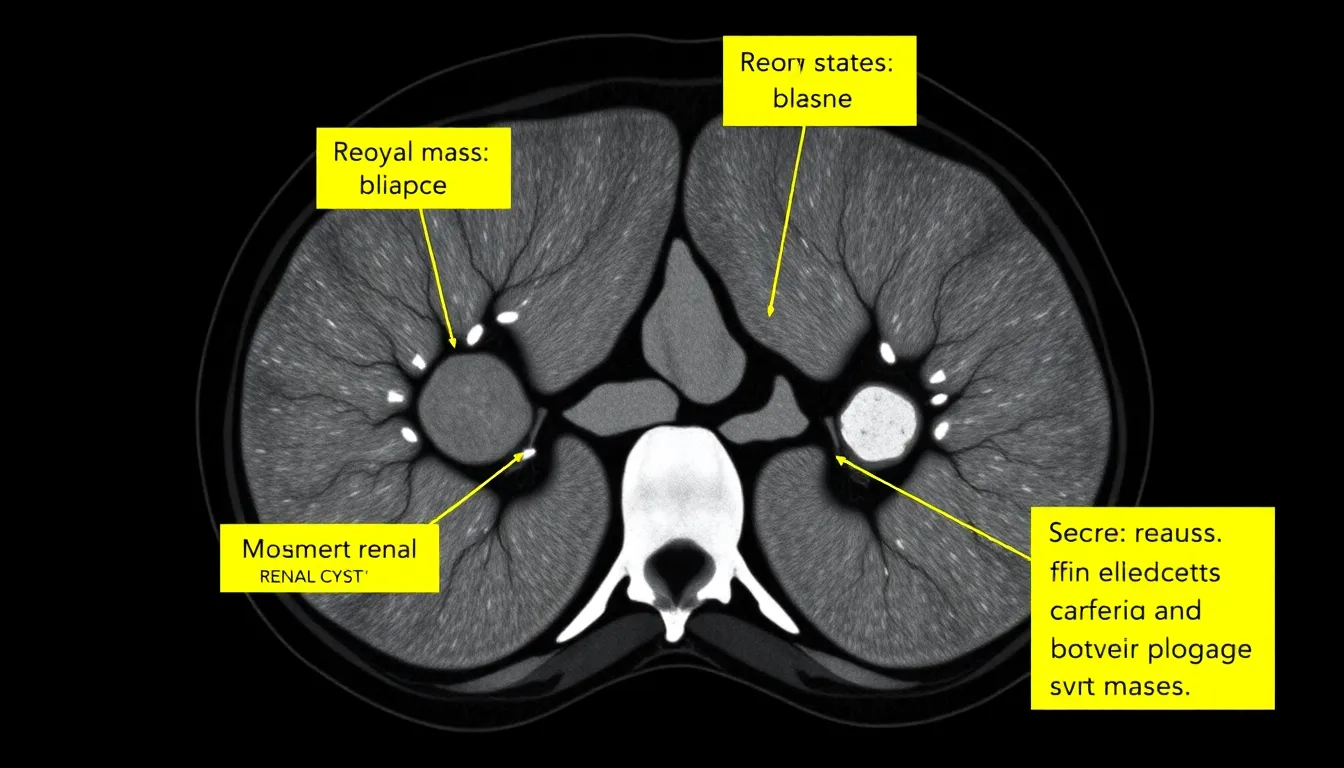

An important factor involves the mass’s characteristics. Size, shape, and density provide crucial information for diagnosis. For instance, a solid mass might raise more red flags than a cystic one, which is often benign. Evaluating these features helps determine whether further investigation or monitoring is necessary.

Benign masses include renal cysts, angiomyolipomas, and oncocytomas. Cysts appear as fluid-filled sacs and are usually harmless. Angiomyolipomas consist of blood vessels, muscle, and fat, while oncocytomas are tumors that often do not require treatment. Malignant masses, such as renal cell carcinoma and transitional cell carcinoma, arise from kidney tissues and pose significant health risks. Determining the nature of the mass plays a vital role in treatment decisions.

Mass characteristics greatly influence diagnosis. Size is a primary factor; larger masses may warrant further examination. Shape helps distinguish benign from malignant masses, with irregular shapes typically indicating a higher risk. Density also matters; a solid mass with high attenuation raises suspicion of cancer. Evaluation of these properties allows for informed discussions between radiologists and physicians, guiding patient management strategies effectively.

Interpreting kidney CT scan results involves assessing various aspects of any detected masses. Radiologists focus on size, shape, and density to determine whether masses are benign or malignant. Benign masses like cysts or angiomyolipomas typically exhibit distinct characteristics not associated with cancer. Malignant masses, on the other hand, may show irregular shapes and increased density. Physicians discuss these findings with patients, providing clear explanations about what they mean for their health. Awareness of these interpretations helps patients understand the next steps in their care and treatment planning.

Benign masses include renal cysts, angiomyolipomas, and oncocytomas. These growths typically don’t pose serious health risks and often require minimal intervention. Malignant masses, such as renal cell carcinoma and transitional cell carcinoma, necessitate prompt evaluation and treatment. Characteristics like size, shape, and density help radiologists differentiate between benign and malignant conditions. A small, simple cyst usually indicates a benign nature, while irregular shapes or significant size may suggest malignancy. The distinction between these types influences the management and prognosis for patients.